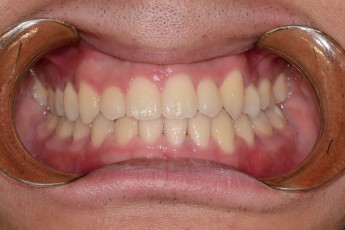

Before & After

Before

After